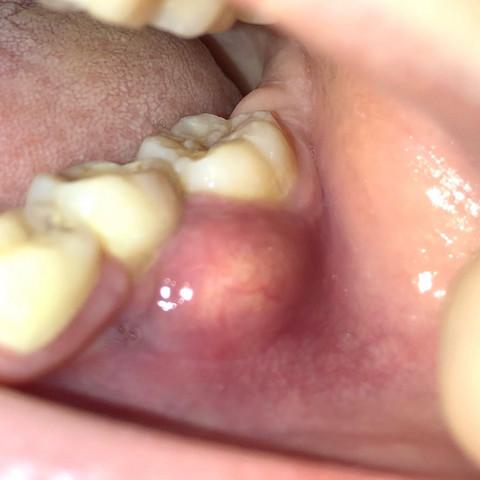

Beule am zahnfleisch ohne schmerzen. Die braucht sie dann auch. In diesen Fällen sollte man am besten zwei bis drei Tage abwarten und schauen ob sich die Situation bessert. Das sieht nach einer stark entzündeten Zahnfleischtasche aus.

Am Zahn und Zahnfleisch können viele Probleme entstehen. Die beuele ist vermutlich ein sich ausbildender abszeß der von alleine nicht besser wird auch die schmerzen werden nicht besser. Der wird die Stelle behandeln und ihr wahrscheinlich Antibiotika verschreiben.

Weitere Auslöser können sein. Eine Eiterbeuleentsteht durch die Entzündung im Knochen und am Zahn. Probleme am Zahn wie Zyste Fistel Eiter Schwellung.

Entweder wurde das Zahnfleisch durch mechanische Reize verletzt oder eine Infektion mit Viren Bakterien oder Pilzen ist schuld an der Entzündung. Die Beule ist unnachgiebig aber sie ist ja noch ein Kind. Diese Bakterien können einen Abszess verursachen selbst wenn die Zähne gesund und frei von Löchern sind.

Mit der richtigen Betäubung ist die Behandlung vom Zahn ohne Schmerzen. Eine Schwellung des Zahnfleisches ist ein Anzeichen für eine Entzündung.

Es entsteht ein sogenannter Abszess. Sie sollten jedoch sofort Ihren Arzt anrufen wenn Sie zusätzlich zu einer Beule eines der folgenden Symptome bemerken. Werde auf jeden Fall zum Zahnarzt müssen habe aber eine riesen Angst das sich nun eine Wurzelentzündung oder sogar noch schlimmeres dahinter verbergen könnte. Damit muss sie DRINGEND zum Zahnarzt. Das kann an einer leichten Entzündung oder einer Wucherung liegen. Zudem ist das frühe Stadium einer Infektion des Zahnfleisches meist schmerzlos. Ist ein Zahn oder ein Zahnnerv entzündet schmerzt nicht nur der Zahn selbst. Die braucht sie dann auch. Fragt am besten den Ärztlichen Bereitschaftsdienst Tel.

Sie sollten jedoch sofort Ihren Arzt anrufen wenn Sie zusätzlich zu einer Beule eines der folgenden Symptome bemerken. Mit großer wahrscheinlichkeit ist der zahn abgestorben kann auch symptomolos passieren. Deshalb empfindet der Betroffene keine Schmerzen obwohl sich die Entzündung mit großer Wahrscheinlichkeit schon tief in den Kiefer hinein vorgearbeitet hat. Fragt am besten den Ärztlichen Bereitschaftsdienst Tel. 116 117 wer heute Zahnärztliche Bereitschaft macht. Damit muss sie DRINGEND zum Zahnarzt. Weitere Auslöser können sein.